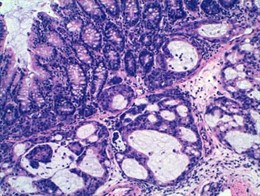

Tumor de colon cuyo crecimiento está inhibico con enoxacina

IDIBELL